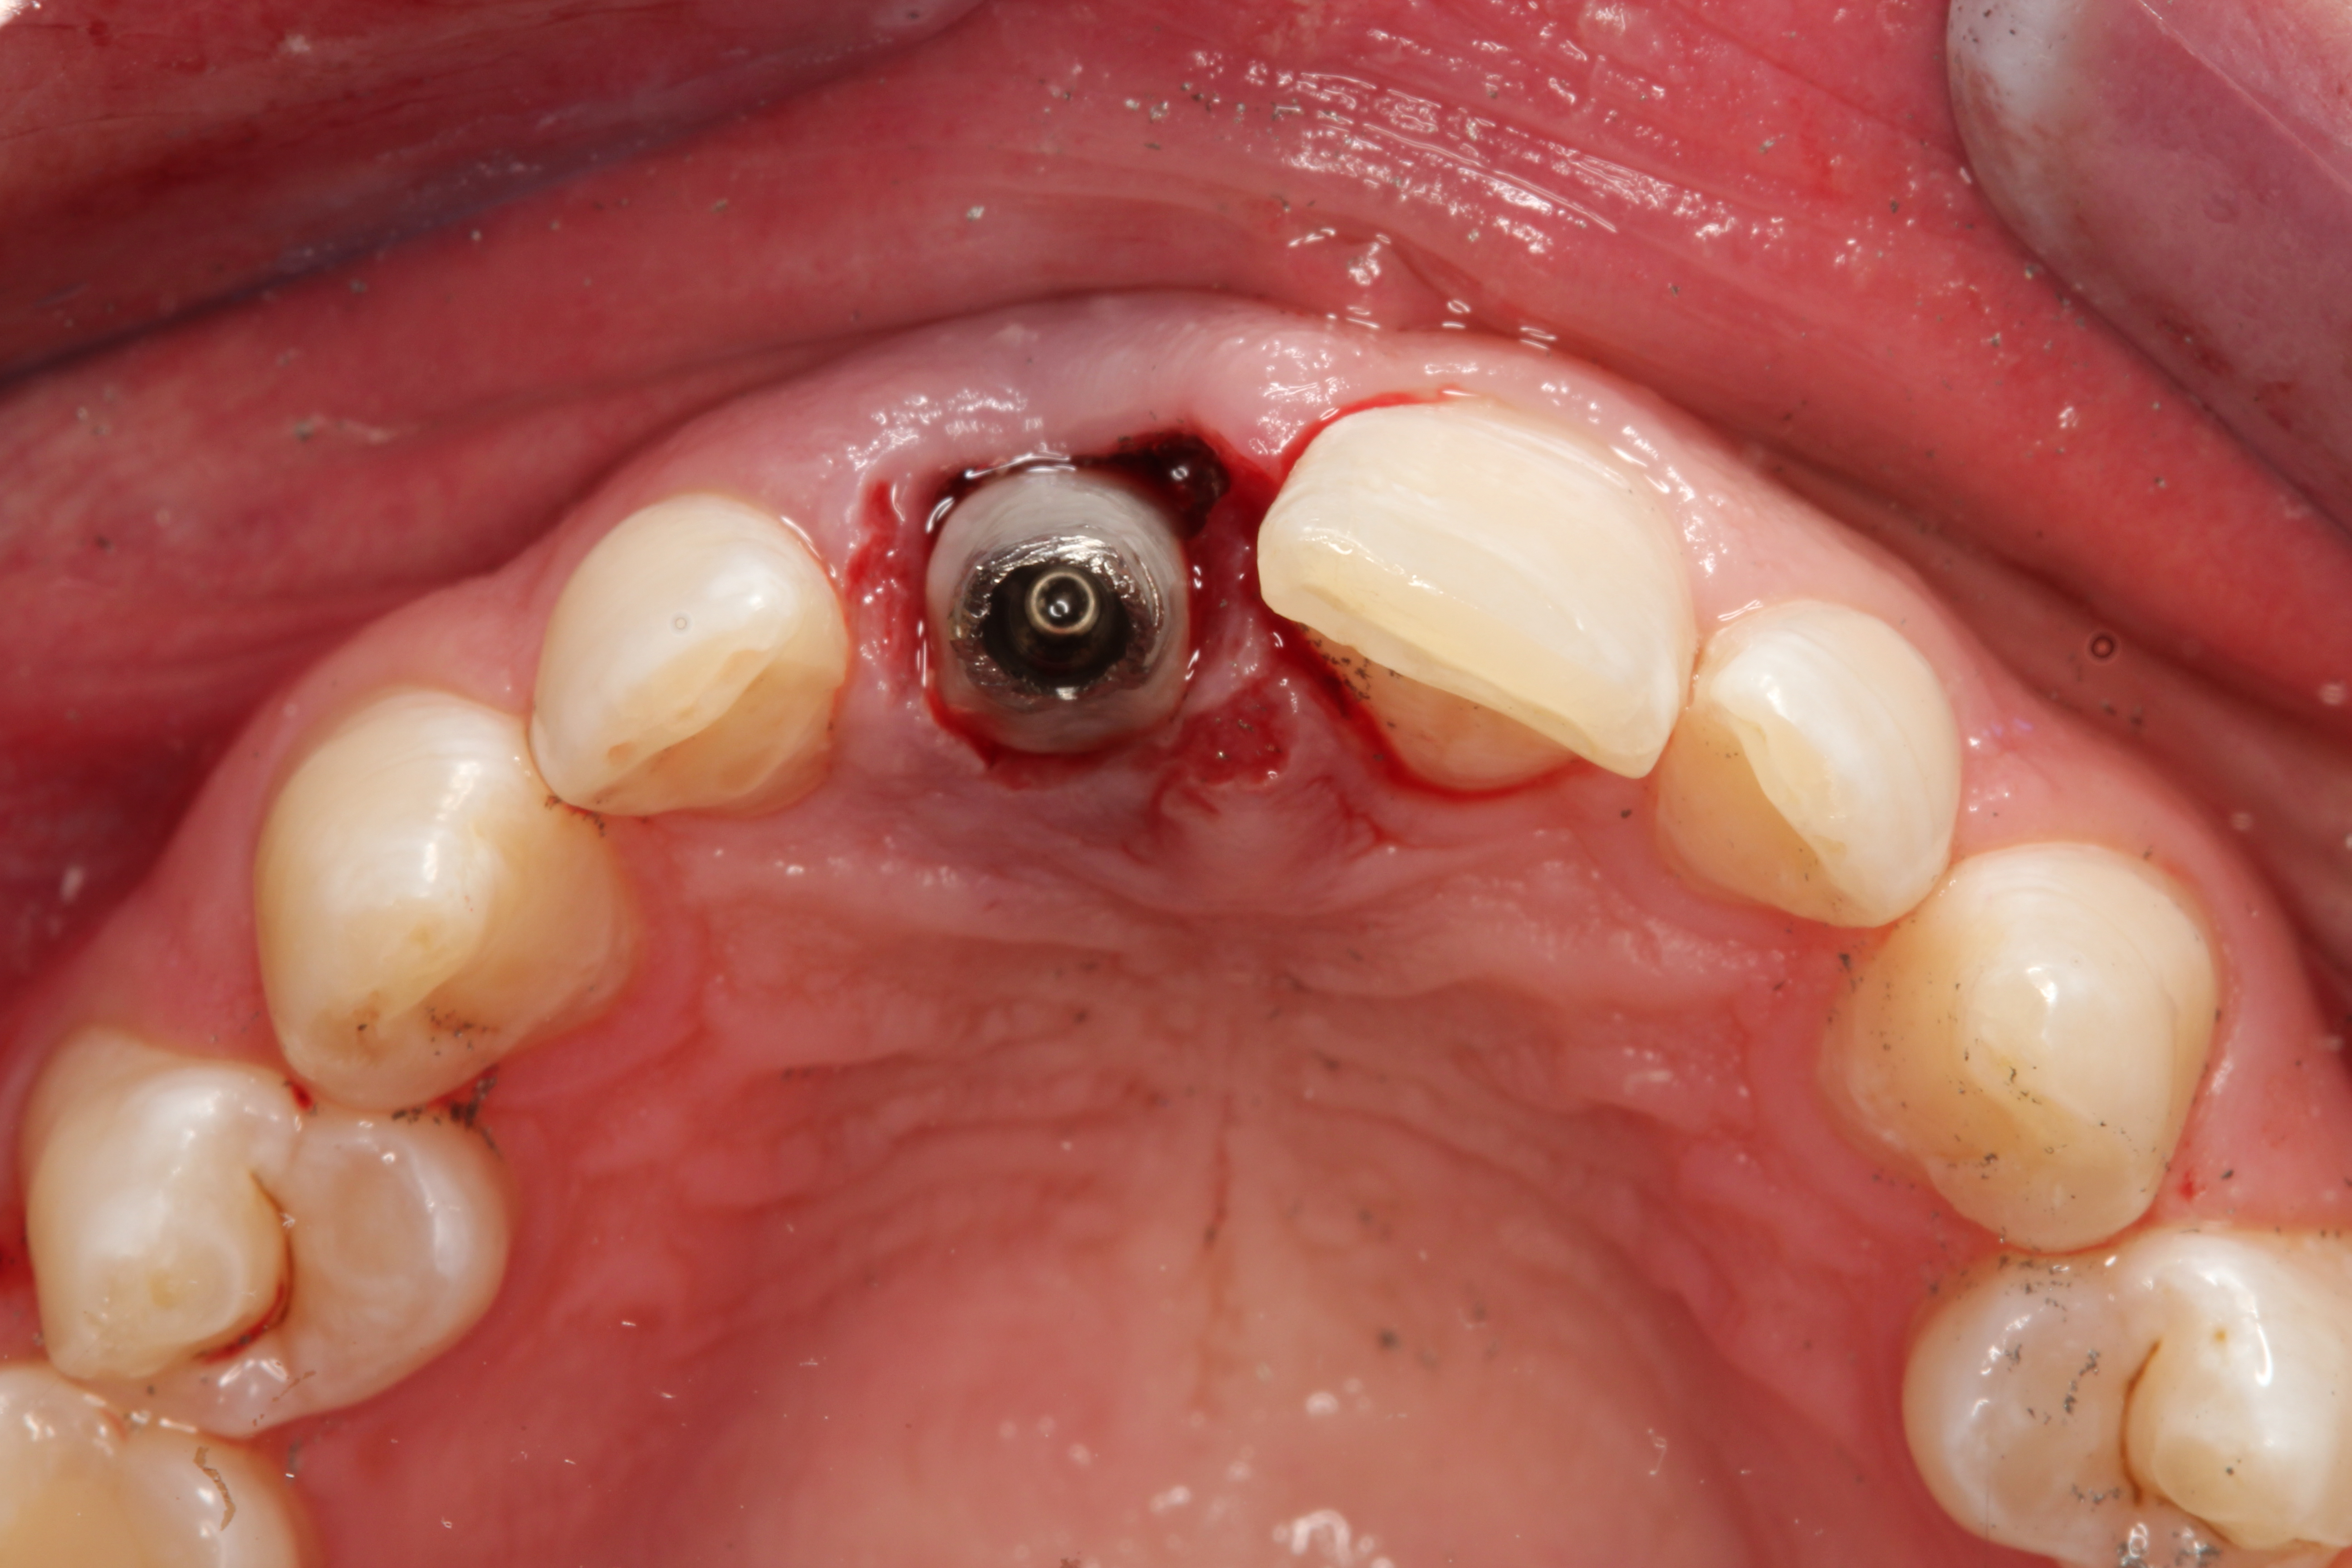

Fig 9. Occlusal view, implant placement after extraction, buccal plate intact.

Figure 9

Due to the young man's college schedule and consequent time constraints, he was appointed the next day. A surgical guide was not used because there was limited time and there was an appropriate amount of thick soft-tissue profile, measured amount of bone volume based on the CBCT, and virtual placement of the dental implant. Figure 7 and Figure 8 showed the measurements to be more than 2 mm buccal and lingual to the proposed implant placement. The interproximal dimensions mesial and distal to the implant proposal were greater than the 1.5 mm previously mentioned in this article. The CBCT images provided the spatial dimensions and a mental awareness regarding implant placement angulation. The final position was predetermined and acceptable for the considerations necessary in choosing the abutment (zirconia or titanium) and final restoration. Because the implant had appropriate bone length and abundant 360-degree bone volume, minimal augmentation was needed. The natural clinical crown was used to provide an ideal emergence profile to enhance the soft-tissue architecture. Atraumatic tooth extraction was extremely helpful in the development of this treatment plan. Having 1.5 mm to 2 mm of facial bone available after the extraction would facilitate exceptional healing and long-term results. Figure 9, occlusal view, depicted a thick soft-tissue profile and properly placed implant within the arch form.